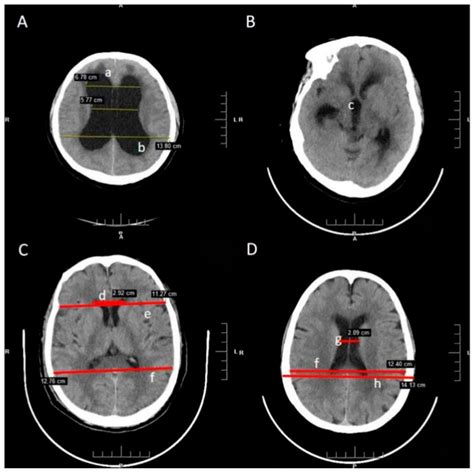

A Normal Ct Head Png serves as a benchmark for comparing abnormal scans. It helps radiologists and neurologists identify deviations from the standard anatomy, which can indicate various medical conditions. The normal scan provides a clear picture of the brain’s structure, including the ventricles, cerebral cortex, and other critical areas.

Interpreting a Normal Ct Head Png involves a thorough understanding of brain anatomy. Radiologists look for several key features:

• Ventricles: The ventricles are fluid-filled spaces in the brain. In a normal scan, they should be symmetrical and of normal size.

• Cerebral Cortex: The cerebral cortex should appear smooth and uniform, without any signs of atrophy or lesions.

• White Matter: The white matter should be intact, without any signs of demyelination or other abnormalities.

• Blood Vessels: The major blood vessels should be clearly visible and free of any blockages or aneurysms.